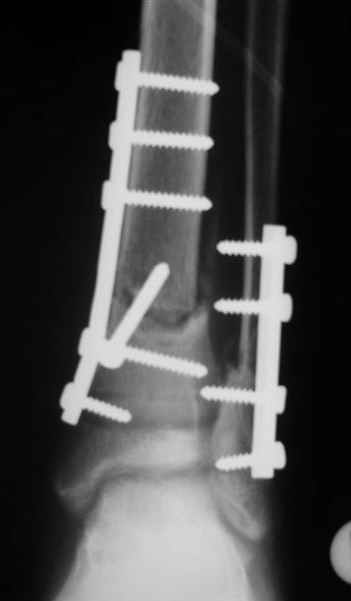

Помятуя наш недавний разговор о фиксации м.б. кост, высылаю послеоперационные картинки..

Напомню- разбирали случай 17 летнего молодого человека перелом дист тиб.фиб. хирургия после 3 недель с момента травмы( безуспешные попытки закрытой репозиции) Раны заживают первичным натяжением, занимается физиотерапией, пока никаких проблем не наблюдается

Согласный я с тобой:-)) есть остаточная вальгусная деформация (по снимку видно перекрывание дист. фрагментом б.б по латеральной поверхности проксимальноо фагмента на 2-3 мм и наружная лодыжка репонирована с укорочением, судя по прямой проекции. Необходимость использования интраоперационно дистрактора была бы оправдана (вручную было непросто *вытянуть* дистальный отломок.)

На мой взгляд, Ваша демонстрация неожиданно добавила перцу. Если память мне не изменяет, я говорил об отсутствии показаний к остеосинтезу малоберцовой.

Сейчас можно заикнуться о вредности этой манипуляции с точки зрения риска фиксации в неправильном положении, как это получилось у Вашего пациента. Сначала фиксировали большеберцовую, и надо было на этом остановиться, ин май хамбл опиньон. Потом при закручивании винтов на мощнейшей второй пластине сустав увело на вальгус. С учетом того, что пацану всего 17, я бы удалил пластину с малоберцовой и попытался тем или иным способом устранить смещение, пока не срослось.

Все так и не совсем - последовательность процедуры( я уже, кажется, упоминал)открыл зону перелома б.б., оценил мобильность фрагментов при очевидном смещении - отрепонировать вручную не получилось и понятна причина. Открыл область перелома м.б. отрепонировал( как мне показалось вполне адекватно) и фиксировал пластиной. ПРи ревизии зоны перелома б.б. положение фрагментов улучшилось, но сохранялось остаточное смещение дистального фрагмента кпереди хоть и незначительное, которое устранил и фиксировал межфрагментарным винтом, далее пластина. Конечно, следовало интраоперационно проконтролировать РГ, откровенно говоря, не ожидал, что постоп контроль будет так выглядить, показалось , что достигнутая репозиция вполне адекватна.....

Согласен с вашей рекомендацией (пока парень отпросился на выходные домой, а по возвращении будет разговор) Кстати ваш аргумент в пользу важности адекватной репозиции м.б. .... Поскольку оставшийся вальгус ничем , кроме, как укорочением м.б не объяснить - для ревизии приготовлю дистрактор.